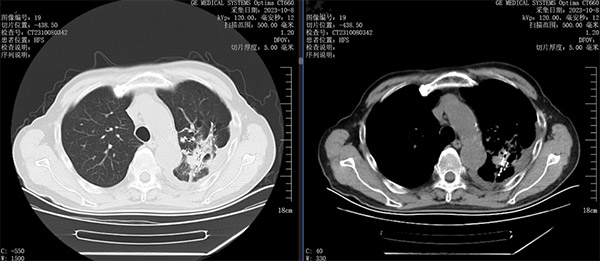

综合患者的状况,首选治疗方案是使用肺癌靶向药物,根据基因检测结果EGFR19外显子缺失突变,丰度1.5%,给予阿法替尼靶向治疗。口服靶向药期间,患者定期复查,一年半后逐渐出现咳嗽、喘息气短,复查肺CT发现左肺上叶病灶增大,同时出现左侧胸膜转移,左肾上腺转移。根据肿瘤进展情况,应更换靶向药物及静脉化疗,不过家属及刘大爷都拒绝进行化疗。根据肿瘤的分期、阶段,再结合患者身体状况,介入科团队拟采用放射性粒子植入术,以控制肿瘤的进展,家属及患者在详细了解方案后对粒子植入的疗法也非常认可。经过充分的术前讨论及准备,手术如期开展,术中按照预先拟定好的TPS计划系统均匀布放43颗粒子,仅30分钟成功实施粒子植入术。术后半个月刘大爷的咳嗽明显减轻,左肺病灶从83X49mm明显缩小到58X21mm。粒子植入术后至今,患者状态一直良好。

放射性粒子植入术后1个月复查左肺病灶从83*49mm缩小到58*21mm,疗效CR

两年多的抗癌之路,粒子照射控制病灶,配合靶向药物治疗,真正意义上实现了患者高质量的带“瘤”生存。在消灭肿瘤的路上,我们始终遵循MDT多学科诊疗模式,拒绝单一治疗方式,在最佳的时间,选择最适合患者的治疗方式,为患者制定准确的治疗计划,提供最合适、最恰当的诊疗方案,一站式解决肿瘤难题,让肿瘤患者不走弯路!